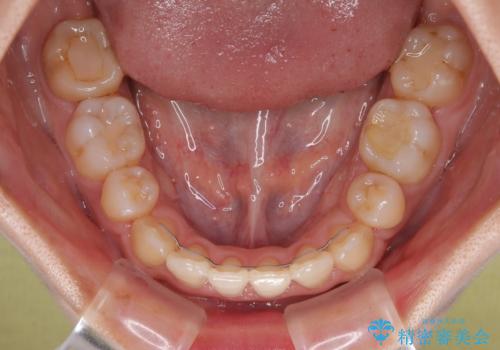

急速拡大装置 狭い骨幅を拡大した上で、口元の突出感を改善する抜歯矯正治療

単純に上下左右の第一小臼歯4本を抜歯して口元の突出感を改善することも考えられましたが、上顎骨よりも下顎骨の幅が広いため、より良い咬み合わせを達成することを目的として、急速拡大装置を用いて上顎骨を拡大することとしました。

歯列矯正では基本的に骨格を改善することはできませんが、急速拡大装置(MARPE)を使用することで上顎骨を側方に拡大させることができ、咬合状態を大きく改善することができます。